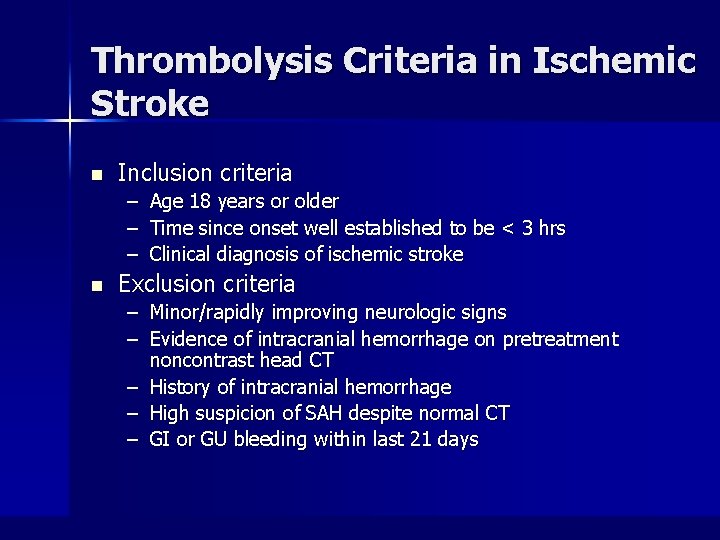

Thrombolysis Criteria in Ischemic Stroke n Inclusion criteria – Age 18 years or older – Time since onset well established to be < 3 hrs – Clinical diagnosis of ischemic stroke n Exclusion criteria – Minor/rapidly improving neurologic signs – Evidence of intracranial hemorrhage on pretreatment noncontrast head CT – History of intracranial hemorrhage – High suspicion of SAH despite normal CT – GI or GU bleeding within last 21 days